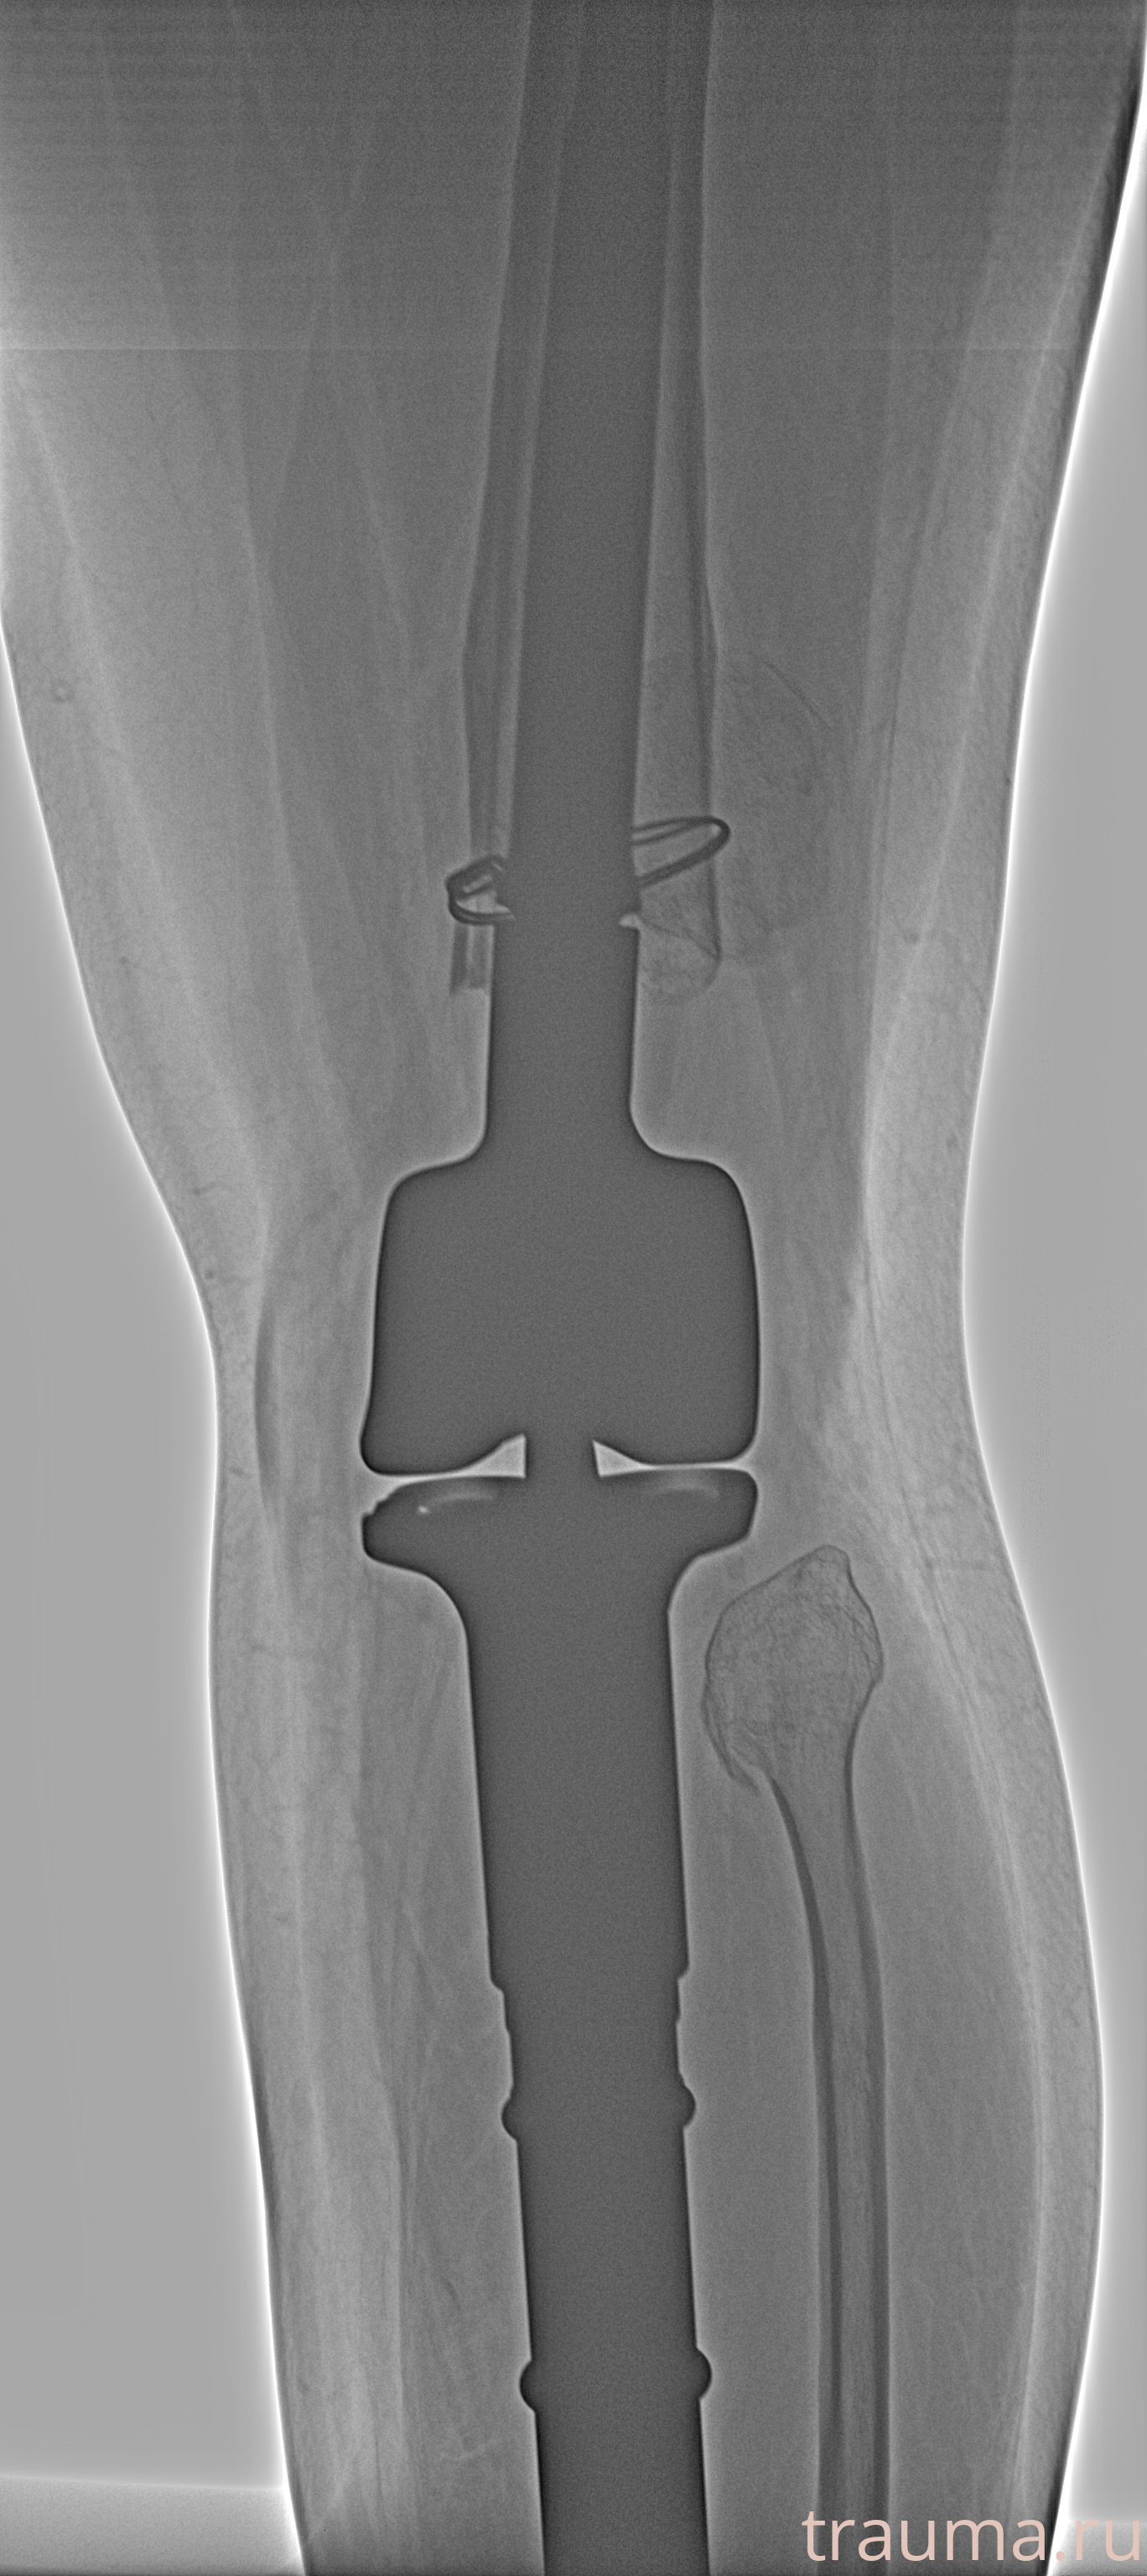

Рентгенограммы

Рентген на дому: по вашему адресу приезжает врач-рентгенолог, травматолог-ортопед с мобильным рентгеновским аппаратом, проводит диагностику травмы или заболевания, делает необходимые рентгенограммы, дает рекомендации по дальнейшему лечению. Получить качественные снимки в домашних условиях возможно благодаря уникальной методике, разработанной МосРентген Центром для института  Склифосовского